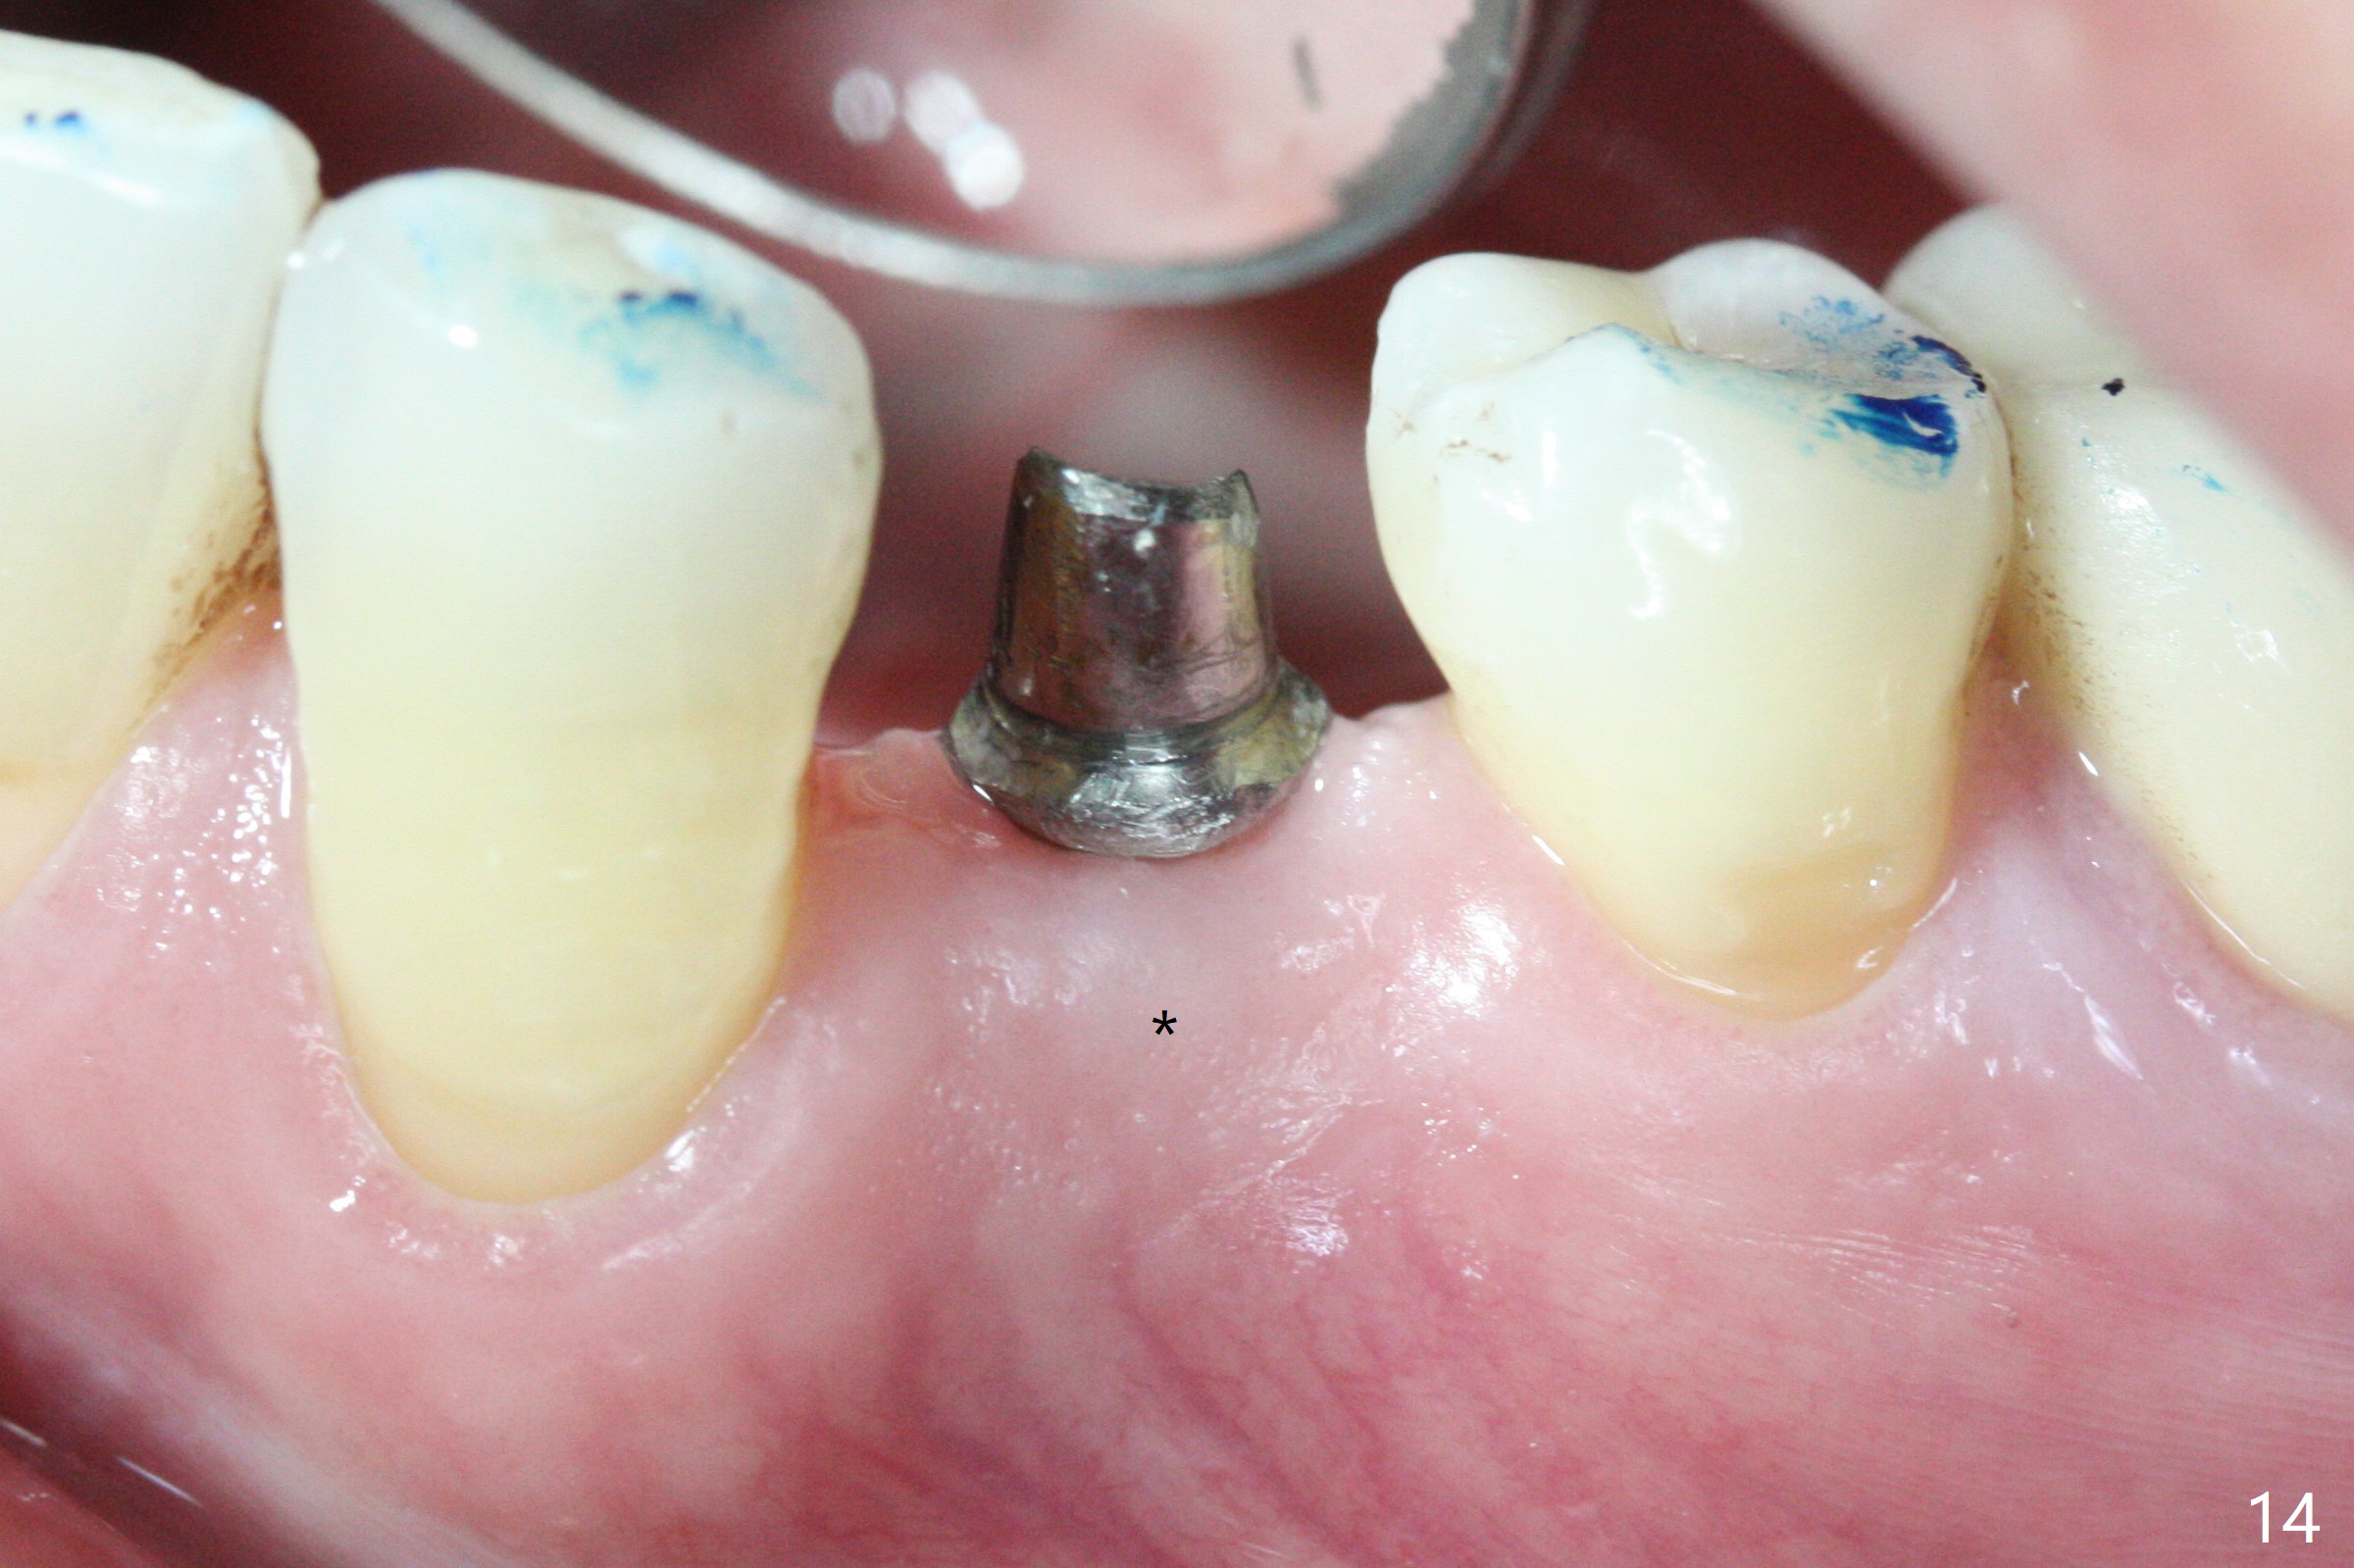

The residual root at #21 seems to be buccally positioned (Fig.1 *).  The initial osteotomy is established with the 1.6 mm drill at 11 mm (Fig.2).  Later the depth increases to 13 mm.  The initial osteotomy is found to be too lingual, but experience shows that as osteotomy increases in diameter, the trajectory would shift buccally due to the thick lingual plate (slope).  When 3.3 mm Magic drill reaches 11 mm, the patient feels pain.  It is probably due to the dense bone.  A 4x11 mm IBS implant cannot be seated due to high torque; it is removed.  The osteotomy is increased with 3.8 mm drill.  The implant is re-seated with >55 Ncm; it is over-lingually placed.  Due to failure to seat the implant driver completely, the implant cannot be un-torqued.  A 4.5 mm 15° angled abutment (3 mm cuff) is placed for immediate provisional (Fig.3,4 *).

The implant seems to have osteointegrated 4 months postop (Fig.9).  When a permanent crown is fabricated, it should have normal occlusal and buccal contour (from Fig.11 (provisional) to 12 red and black curved lines) as well as the buccal cervical extension (Fig.12 to cover the buccal gingiva (Fig.10 *).  If the lingual margin of the abutment is too prominent, return the case and the abutment will be changed to the one with 2 mm cuff (existing 3 mm).  The lingual margin of the abutment will be trimmed.  The patient is not pleased with the short buccal margin of the crown after cementation (Fig.13).  In fact the provisional should have been fabricated so that the its buccal margin should be subgingival and within the gingival outline.  It may prevent buccal plate collapse.  In fact the crown dislodges 1 year post cementation.  The lingual margin is prep lower to increase the abutment height.  Impression is taken.  Although the access hole is unnecessary for cementation, it acts as an escape hole so that there is no excess cement cervically (Fig.14-18).